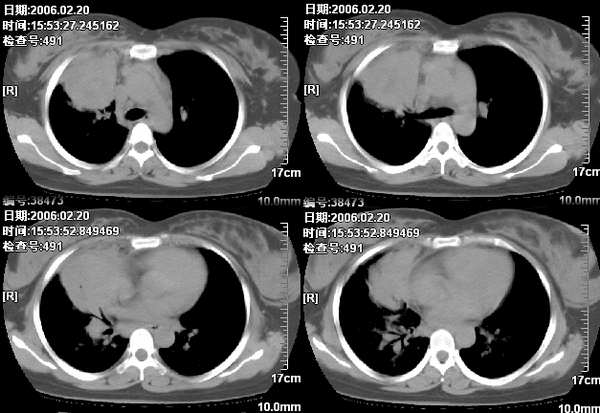

女,28岁咳嗽无痰偶有低烧,化验:白细胞1万零7,血沉正常

图象不错,无肺窗。右肺上叶前段支气管呈鼠尾样,边缘尚光滑,气管前淋巴结肿大,未见空气支气管征考虑占位性病变可能。与大叶性肺炎和早期肺脓肿鉴别,建议抗炎后复查。

右肺上叶前段与中叶见较大团块影。边界较清晰,纵隔隆突前淋巴结增大。考虑1肺部间叶组织肿瘤可能。2感染性病变

我觉得不要把患者年龄作为轻易排除肺癌的依据,病变呈大块状软组织密度,右肺中叶支气管可见中断,右侧肺门增大,要高度警惕肺癌,支气管镜应该能够给出正确的诊断。间质来源的恶性肿瘤尽管可以考虑到,但是从发病率上来说不首先考虑。